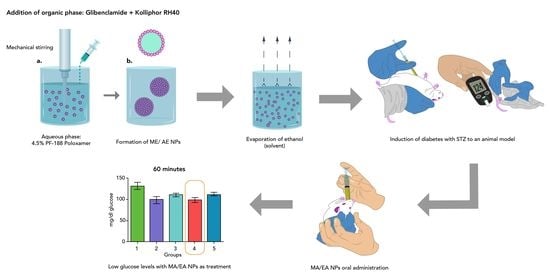

2.4. Nanoparticle Development

2.4.1. Nanoparticles

Aqueous Phase

Organic Phase

NP Obtention

2.7. In Vivo Model

3.1.7. In Vivo Tests